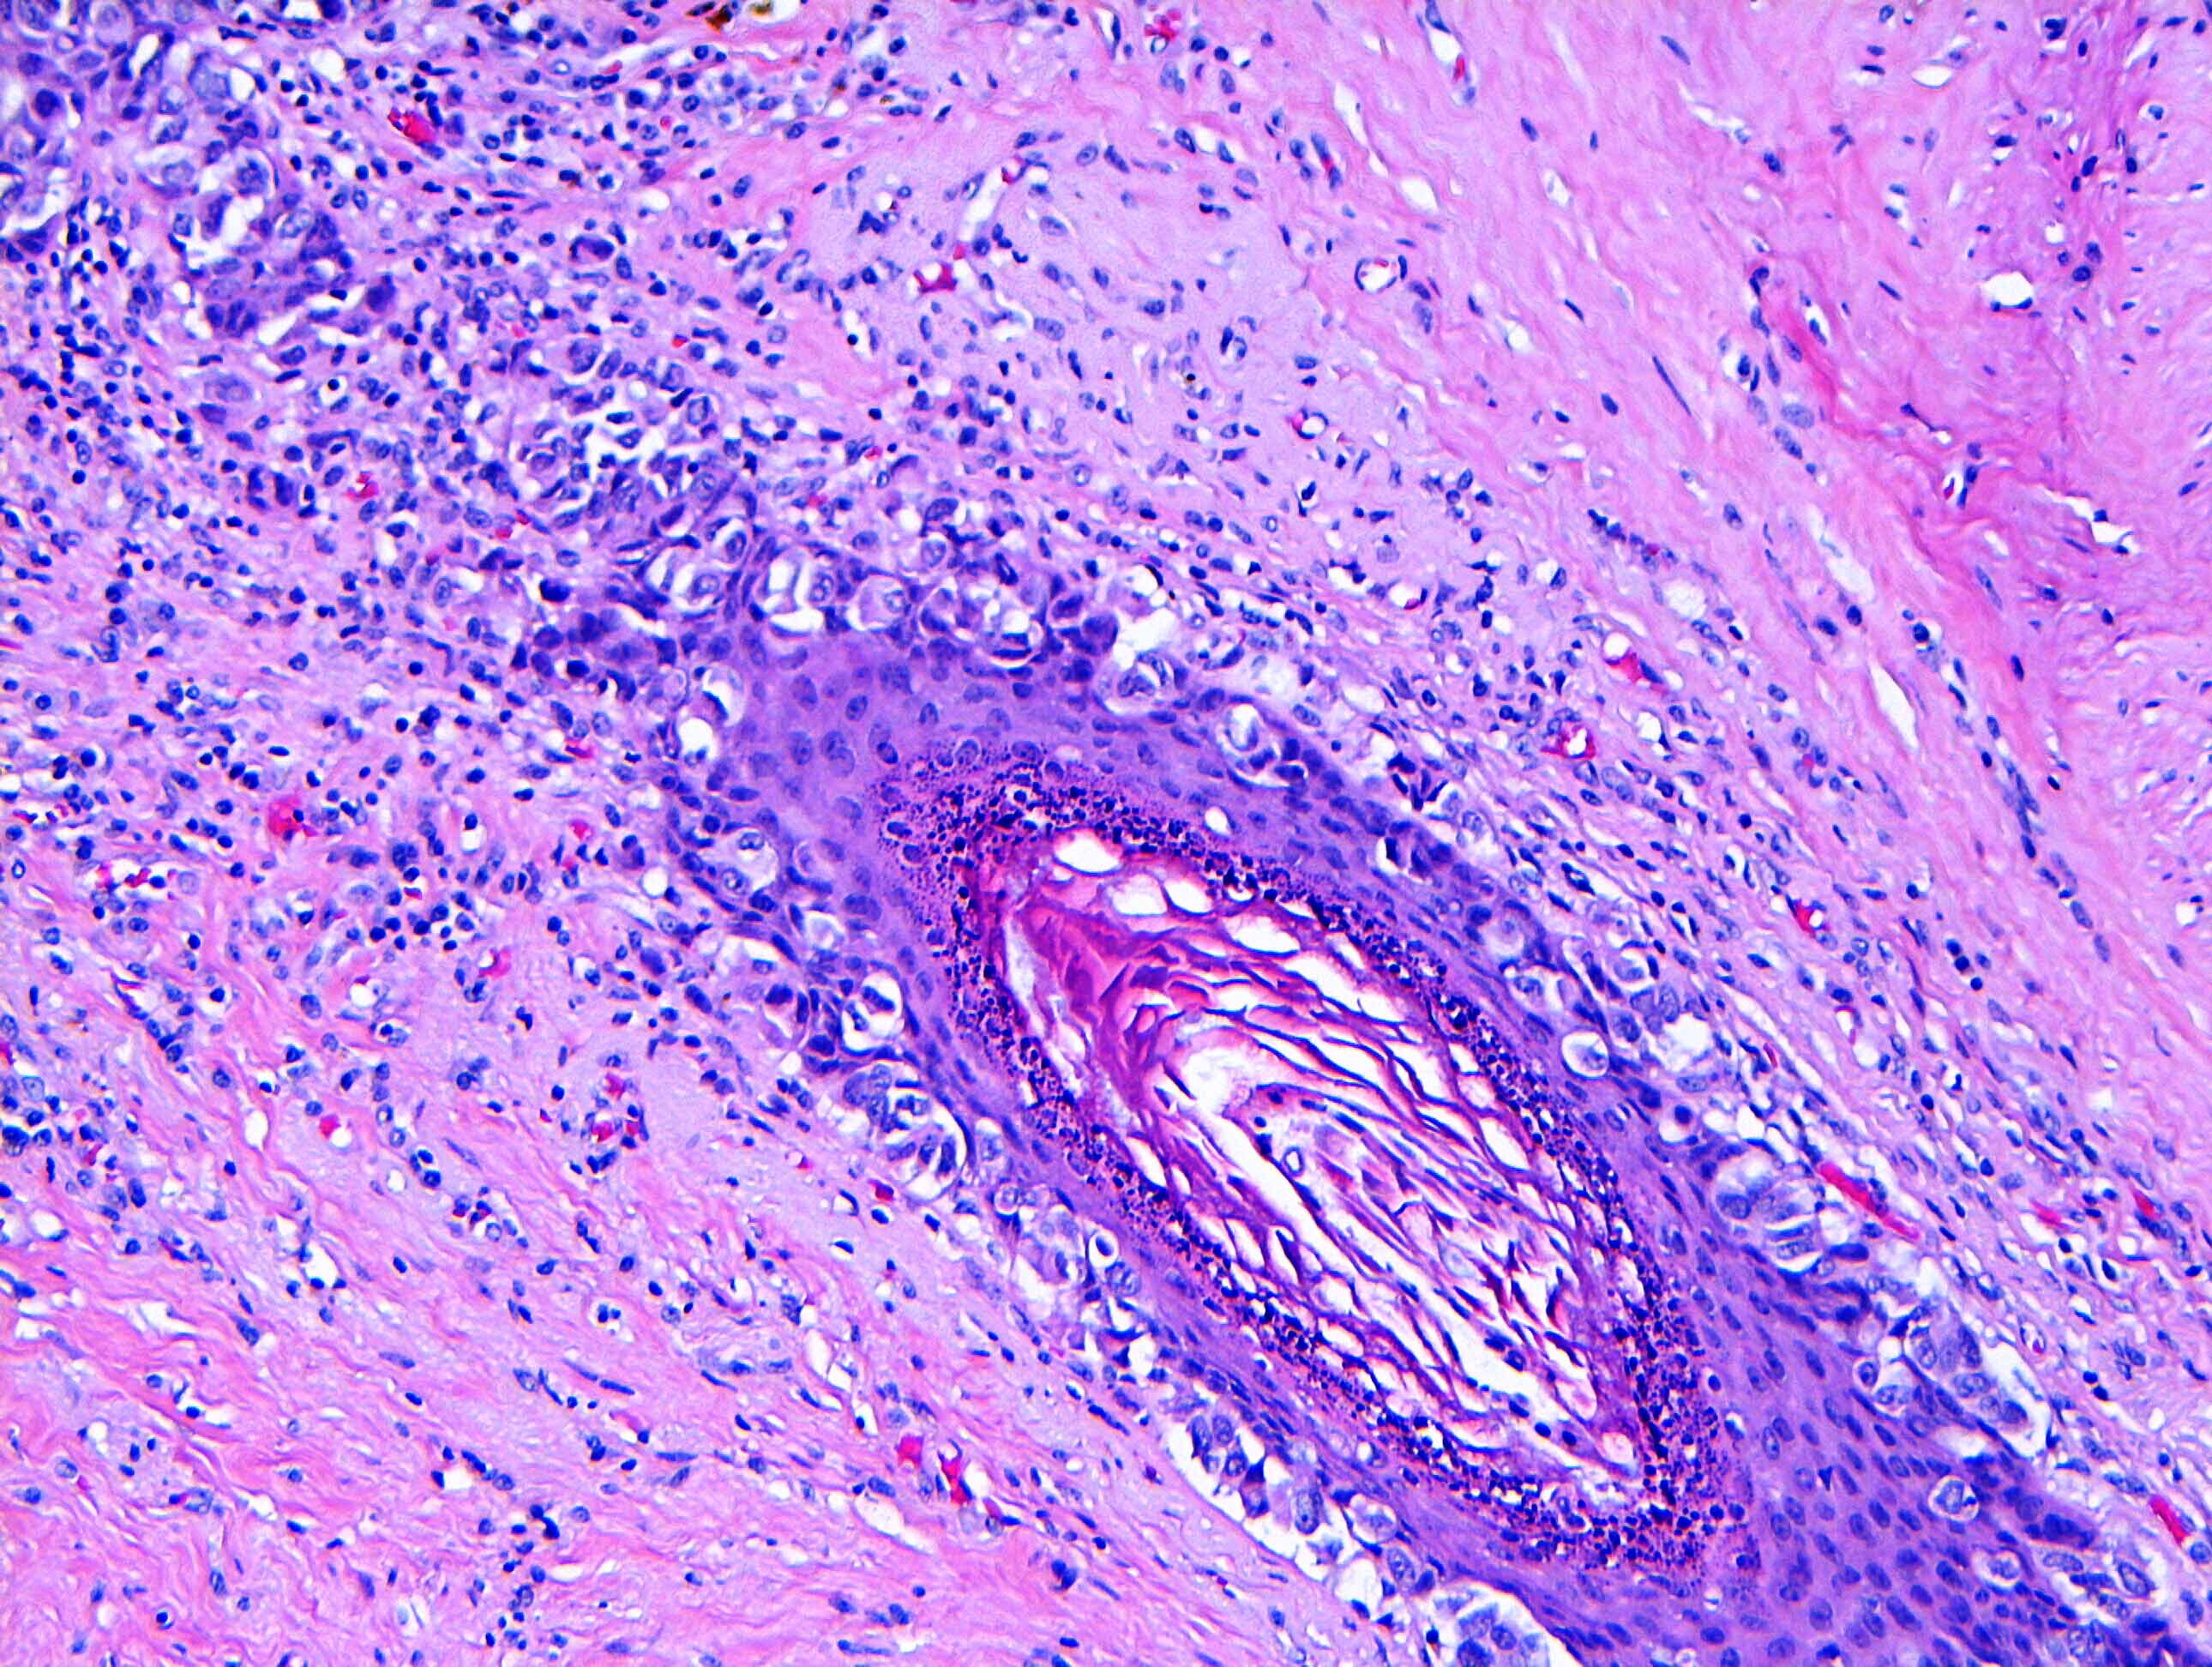

- Single cells or clusters of cells spread throughout the epidermis

- Cells have abundant pale cytoplasm, large irregular nuclei with prominent nucleoli

- Underlying dermis may have chronic inflammation

- Epidermis with hyperkeratosis and possibly ulceration

- Florid cases can show gland formation

- Paget cells may phagocytose melanin, mimicking melanocytes

- Underlying carcinoma is most commonly high grade invasive carcinoma of no special type (NST; 53 - 64%) or DCIS (24 - 43%) (Histopathology 2020;77:181)

Microscopic (histologic) images

Contributed by Anna Biernacka, M.D., Ph.D. and Mary Ann Gimenez Sanders, M.D, Ph.D.